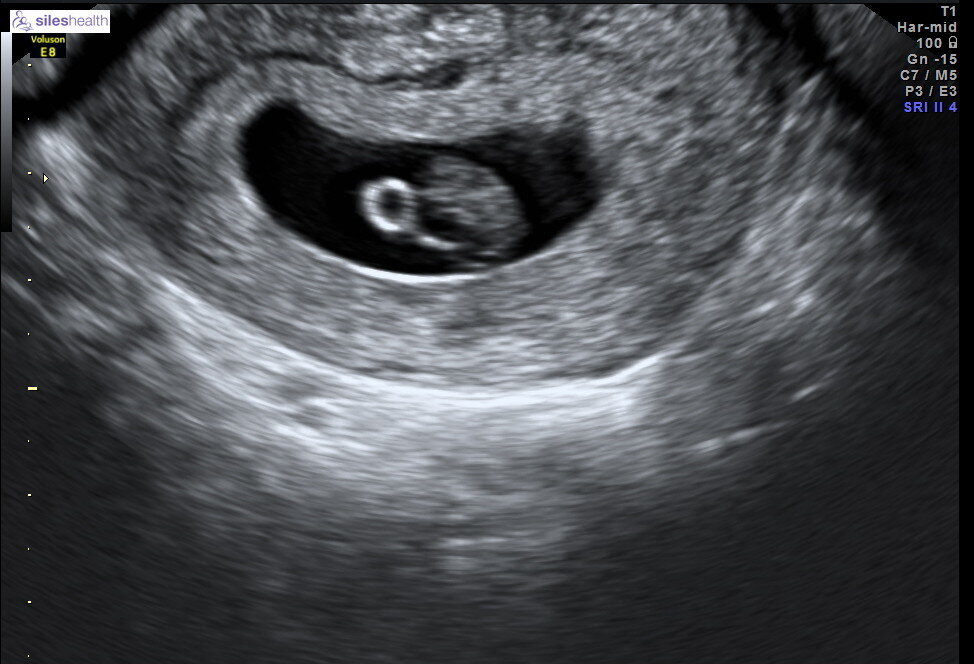

Dating Scan 6 Weeks 5 Days

The fetal pole grows at a rate of about 1 mm a day , starting at the 6th week of gestational age . Thus, a simple and accurate way to "date the fetus" in an early pregnancy is to add the length of the fetal pole (in mm) to 6 weeks . Using this method, a fetal pole measuring 5 mm would have a gestational age of 6 weeks and 5 days . Week 6 Fetal . . .

Using this method, a fetal pole measuring 5 mm would have a gestational age of 6 weeks and 5 days . Crown-rump length (CRL) The crown-rump length measurement is the distance between the top of the embryo and its rump . It can be measured between 7-13 weeks of the pregnancy and gives an accurate estimation of the gestational age . Dating with the . . .

Early scan at 6 weeks 5 days with measurments a few days early . This is my 4th pregnancy (2 mc and a beautiful 3 .5yo boy) . I had an early mc in February so I am super stressed with this new pregnancy and I booked an early scan last Friday . According to my LMP on the day of the scan I should have been 7 weeks exactly, but I know for a fact that . . .